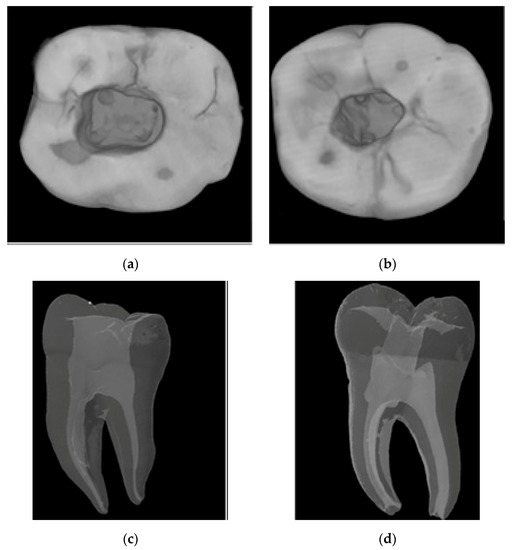

To conduct the first micro-CT scan before access cavity and root canal preparation, the samples were fixed on the turntable of the micro-CT device and scanned with the X-ray source of the device at 80 kVp, 125 mA, 26.7 μm pixel size, and 0.2 rotation. The images obtained after the scan were transferred to the NRecon software (ver. 1.6.10.4, Bruker X-ray, Kontich, Belgium). A total of 1800 two-dimensional sections were obtained from each sample. For the reconstruction, the ring artifact correction was fixed to 7, and the smoothing parameter was set to 3. The beam hardening artifact correction was set to 38%. Contrast settings were kept between 0 and 0.05 for all the samples. Examples of images obtained from micro-CT scanning before cavity and root canal preparation are given in Figure 1.

Figure 1.

Micro-CT images of the lower molar tooth before cavity and canal preparation. (a) A sagittal section. (b) An axial section.

Figure 1 shows the results of the first micro-CT scan. In this scan, teeth were examined regarding fractures, cracks, caries, and radii of curvature to avoid missing possible errors in the dental operating microscope. Samples from micro-CT scanning were placed in silicone molds (Express XT, 3M ESPE, Neuss, Germany) with root tips visible to stabilize and isolate them from the environment during access cavity preparation. The experimental groups were formed according to the type of access cavity and the Ni–Ti file system to be used, as shown in Figure 2.

Figure 3.

Micro-CT images illustrate the differences between traditional and conservative access cavities. (a) Axial section of a traditional access cavity. (b) Axial section of a conservative access cavity. (c) Sagittal section of the conservative approach. (d) Sagittal section of the traditional approach.